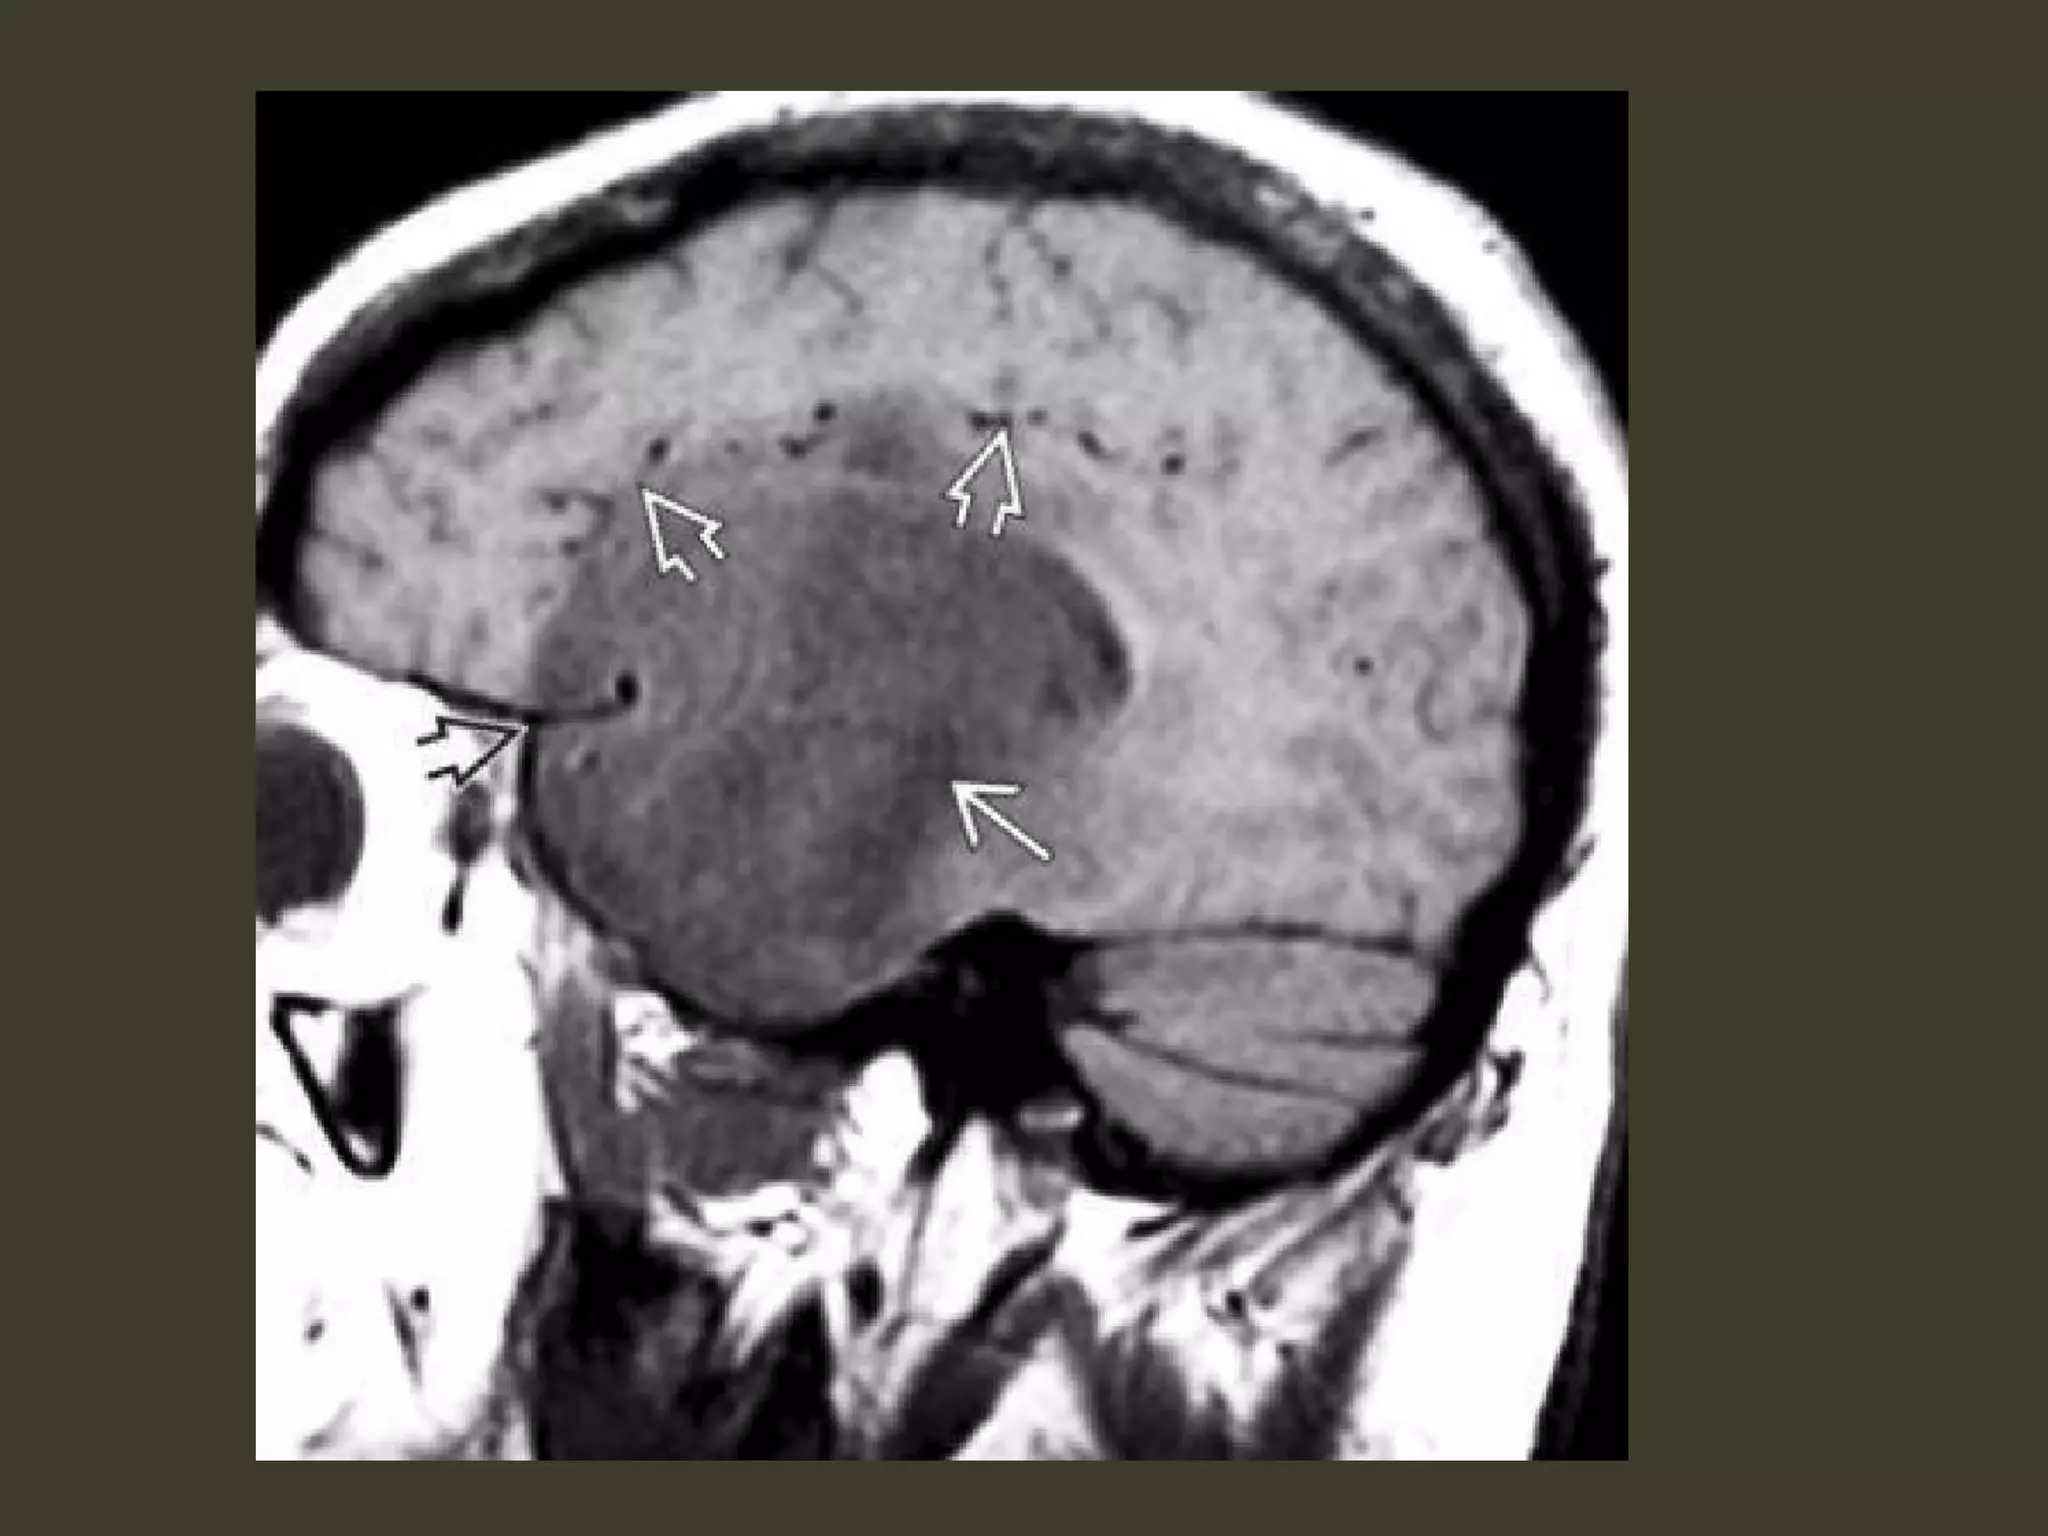

Tonsillar herniation: imaging

• Diagnosing tonsillar herniation on NECT scans

may be problematic.

Cisterna magna obliteration

• MR: much more easily diagnosed

• In the sagittal plane

– the tonsillar folia become vertically oriented

– the inferior aspect of the tonsils becomes

pointed

– Tonsils > 5 mm (or 7 mm in children) below the

foramen magnum are generally abnormal

• especially if they are peg-like or pointed (rather than

rounded)

• In the axial plane, T2 scans show that the

tonsils are impacted into the foramen

magnum

– obliterating CSF in the cisterna magna

– displacing the medulla anteriorly